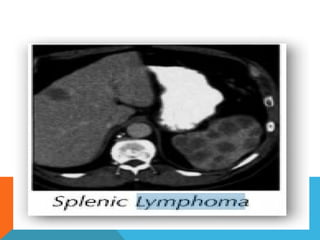

GI lymphoma staging

 I: Tumor confined to bowel wall

 II: Limited nodal spread to local nodes

 III: Widespread nodal mets

 IV: Spread to bone marrow, solid viscera,

liver